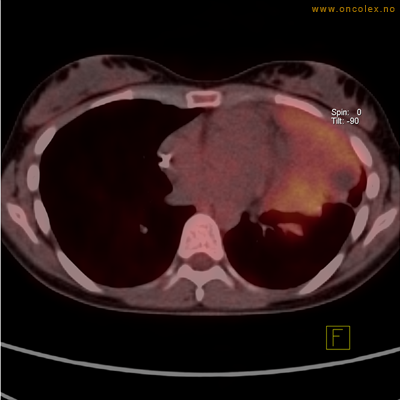

Eksempler på funn

Vev som tar opp mer radioaktivt stoff, synes som hvite områder som lyser opp mer i forhold til annet vev som tar opp mindre sukker.